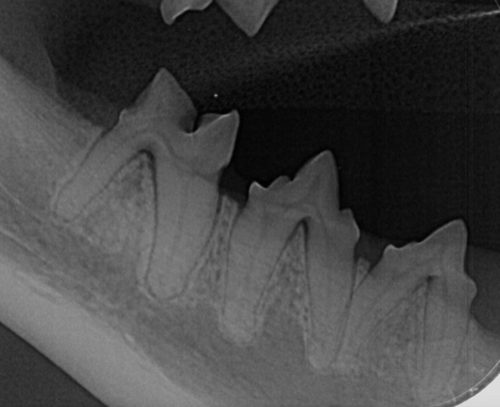

Les affections dentaires ne sont pas toujours visibles. Outre le contrôle en ligne, il est conseillé de faire examiner les dents de votre animal par un vétérinaire en cas de doute. « Nous recommandons un contrôle dentaire annuel », explique Vicky Verreycken. Lors de cet examen, le vétérinaire vérifie la présence de tartre, de décolorations ou de récession gingivale. « Les problèmes dentaires chez les animaux sont souvent faciles à prévenir et à traiter, mais une détection précoce permet de préserver la santé et le bien-être de l’animal, tout en évitant des coûts plus élevés par la suite. »

Images

Vous pouvez télécharger les images ci-dessous en cliquant dessus.